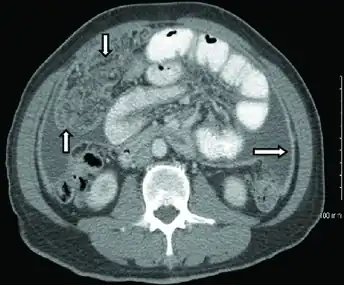

Peritoneal tuberculosis may mimic peritoneal carcinomatosis on CT scan.[4]